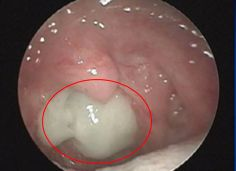

考慮本病時該如何診斷?有上述表現(xiàn)的兒童就診時可檢查鼻竇區(qū)是否有壓痛,鼻竇開口處是否有黃白色分泌物流出,咽后壁濾泡有無明顯增生,嚴重者可呈鵝卵石樣,或者咽后壁是否有黏液附著。鼻竇炎所致鼻后滴漏綜合癥者,鼻竇瓦氏位片CT可見相應(yīng)改變,如鼻黏膜增厚、鼻腔模糊不清、鼻竇內(nèi)出現(xiàn)黏液等。

圖中咽后壁可以看到黃白色分泌物附著